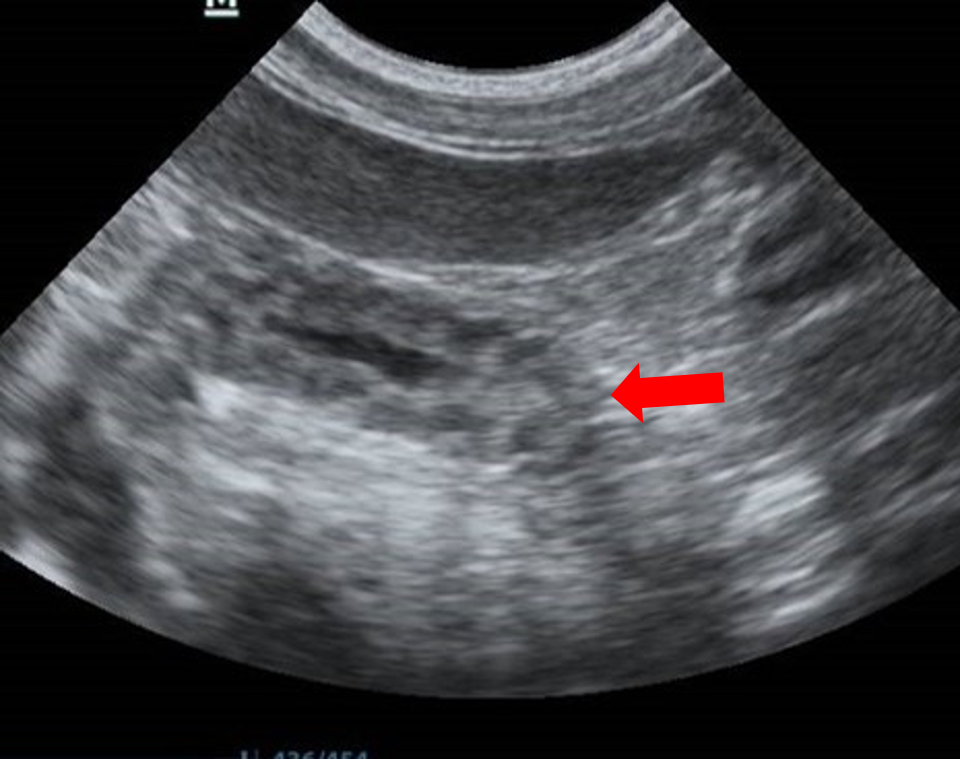

Figure 11. Corrugation – This image shows a section of jejunum (arrow). The intestinal wall has an undulating pattern typical of corrugation. This finding has been described in a number of pathologies including enteritis, peritonitis, pancreatitis and neoplasia. 9 Plication, which is a change associated with foreign bodies particularly linear foreign bodies, appears as a more eccentric arrangement of the intestine compared with the more regular undulation seen in

corrugation.